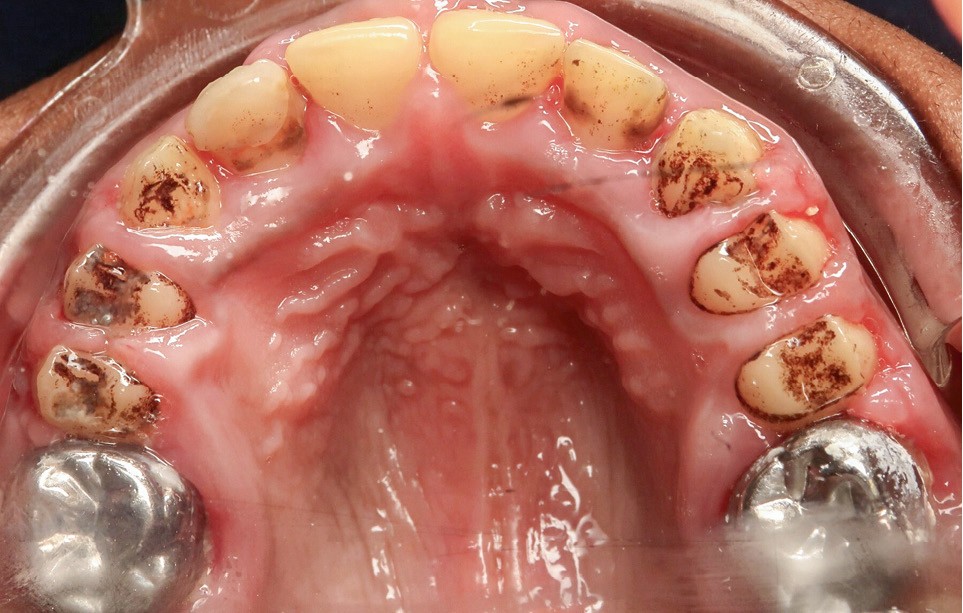

L’examen exobuccal met en évidence un profil dolichofacial et des anomalies majeures de structure dentaire (fig. 1). L’examen intrabuccal (fig. 2) montre :

- une hypoplasie sévère de l’émail ;

- une hyperplasie gingivale inflammatoire ;

- des hauteurs coronaires très réduites ;

- des couronnes pédodontiques sur les premières molaires permanentes ;

- des caries sur 17 et 27 ;

- des défauts d’éruption des quatre deuxièmes molaires permanentes ;

- de nombreux diastèmes et l’absence des dents de sagesse.

La radiographie montre une lésion inflammatoire périapicale d’origine endodontique sur la 26 et l’agénésie des dents 18, 28, 38 et 48.